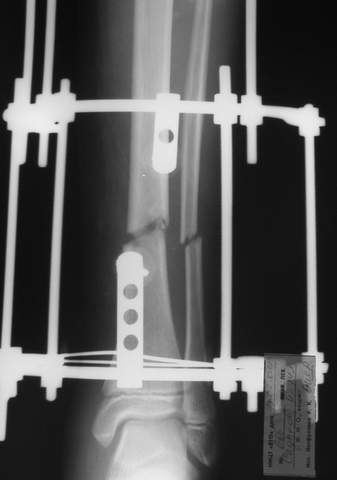

В аттачтах №№ 1 и 2 - примеры, когда 2 кольца не позволили послеоперационно

исправить смещение фрагментов большеберцовой (по ширине и вальгусное).

А казалось бы (#2) - поиграй на штангах и все влетит.

2